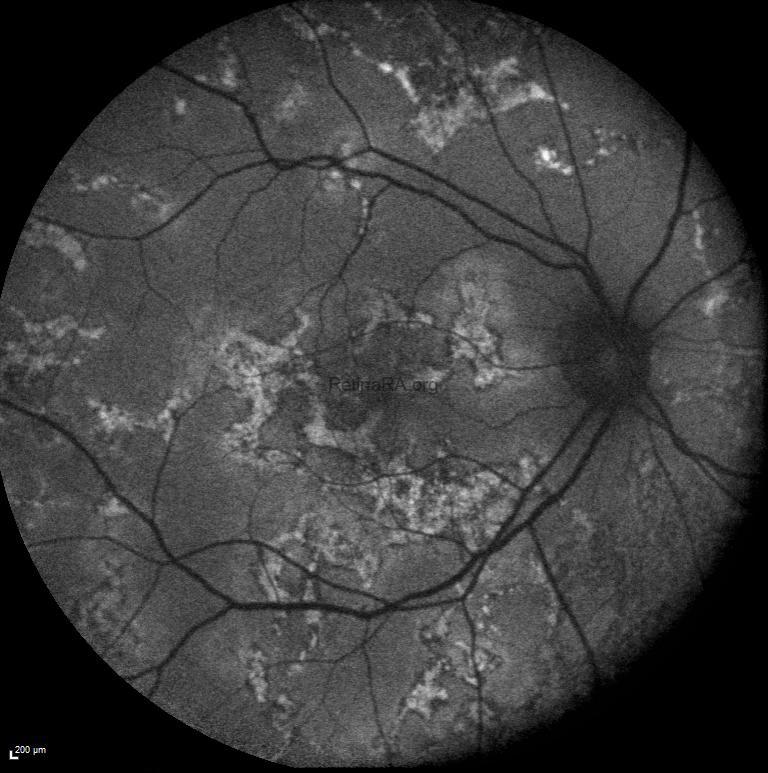

It is noteworthy that active lesion margins are hyperautofluorescent on FAF imaging.

FFA shows a marked hyperfluorescence at the lesion margins.